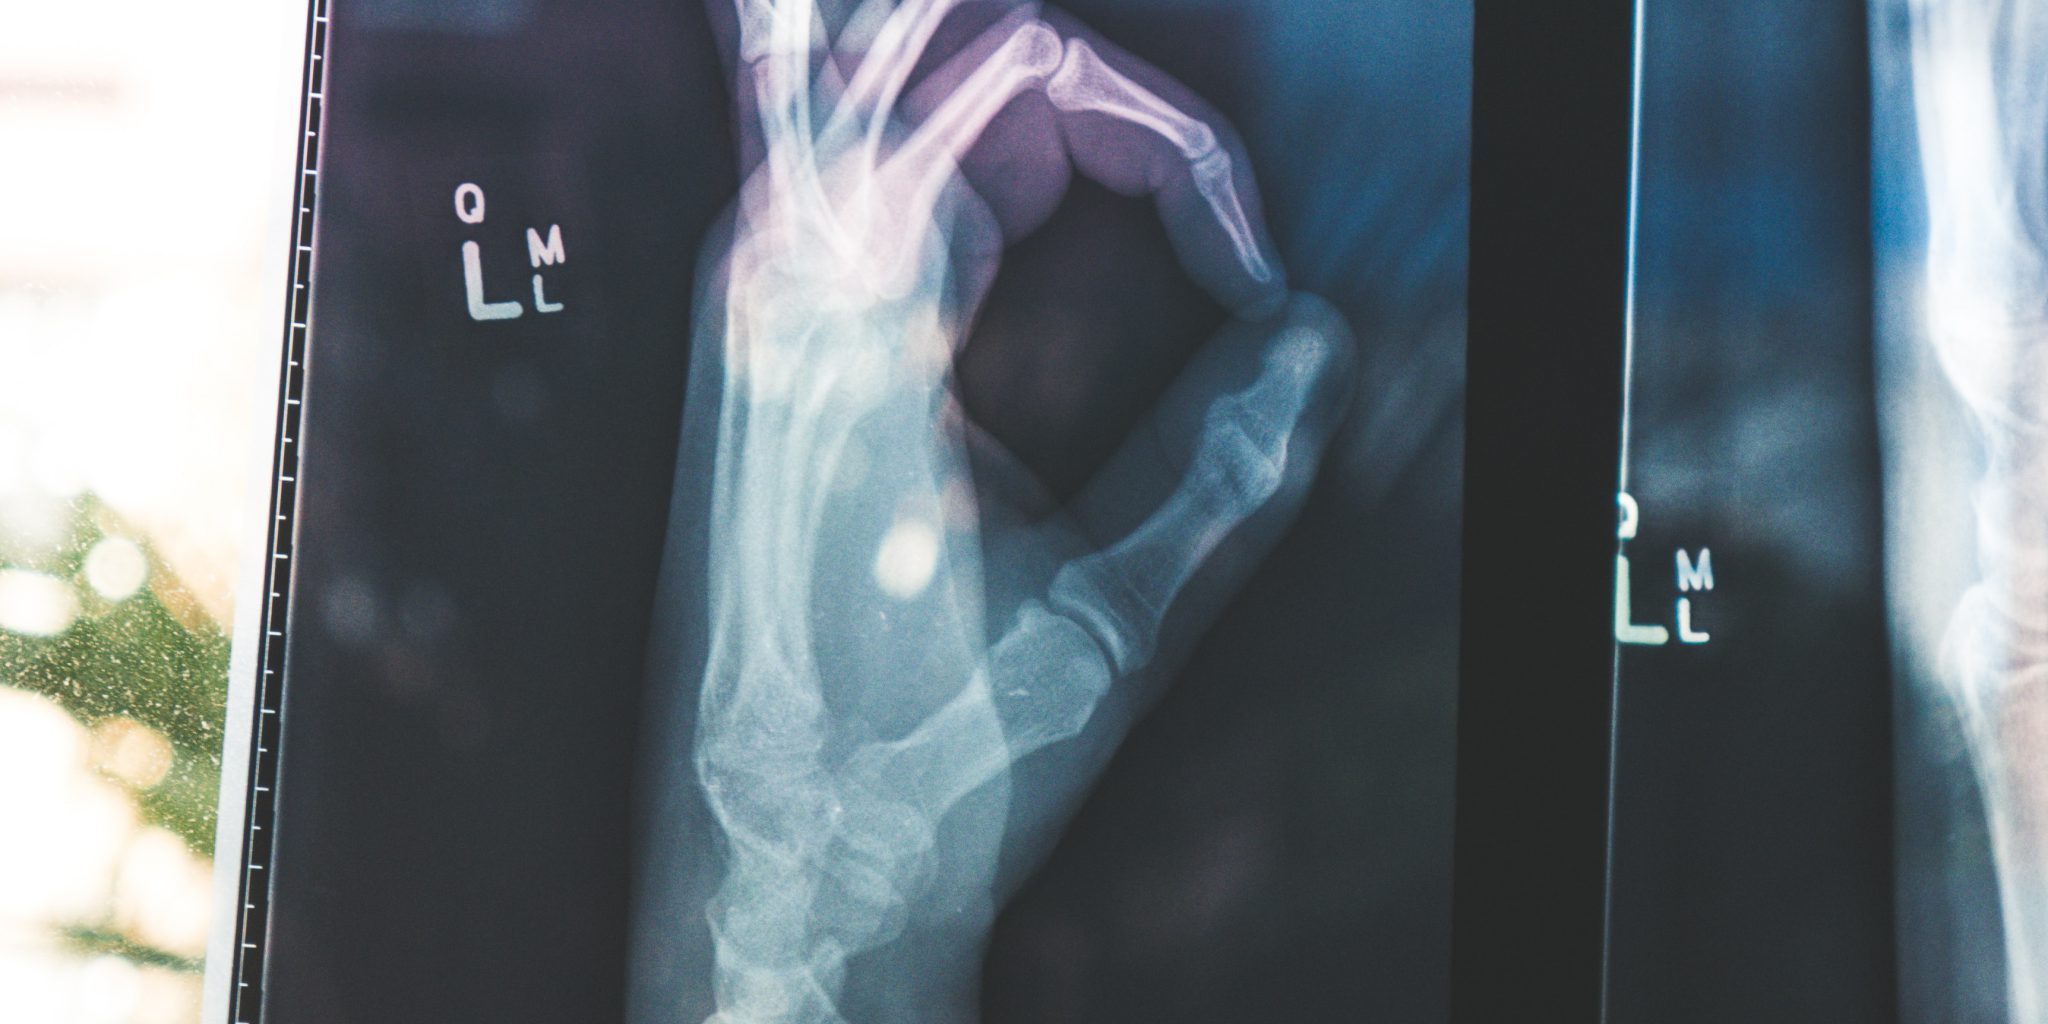

The exponential growth we’ve seen in technology has truly changed the way top industries work, and the healthcare industry is no different. Technological advancements in the health and social care industries have led to the coined term “Smart Healthcare.” As life expectancy continues to increase and the cost of healthcare rises globally, smart healthcare is helping to bridge these gaps and improve patient outcomes. Here’s how it’s being implemented.

Nowadays, most individual patient records have been digitized removing the need for paper files and are referred to as electronic health records (EHRs). The adoption of EHR has encouraged the sharing of patient information among clinicians to lower costs, speed diagnosis, and improve patient outcomes. Professionals are then able to analyze these mass records to predict health outcomes based on trends, to track a treatment’s effectiveness, and to even research which factors could be leading to disease and cancer diagnosis.

It seems certain that we’ve only just seen the very start of how smart healthcare is revolutionizing the industry. The implementation of wearable devices and electronic health records among many other developments are truly transforming the way we collect, manage, and assess medical data.